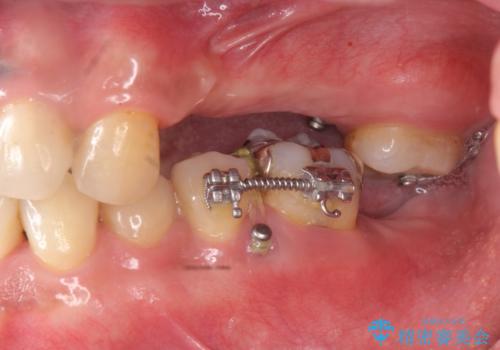

・対合歯の欠損による歯の挺出→マイクロインプラントを用いた小矯正を行うことで咬合平面を是正

噛み合う歯が欠損し長時間放置すると、歯が挺出(歯が伸びてくる)し欠損補綴を行おうにもスペースが足りない場合があります。(クリアランスの不足)

加えて咬合平面の乱れを放置したまま無理やり補綴治療を行うと、特定の部位に過大な力がかかり当該歯を痛めてしまうこともよくあります。

咬合の調和、均等に力がかかることでより長期的な予後を期待することができます。

今回、左下6は頬側歯頚部に虫歯があり圧下を行ったことからクラウンにより補綴を行いました。